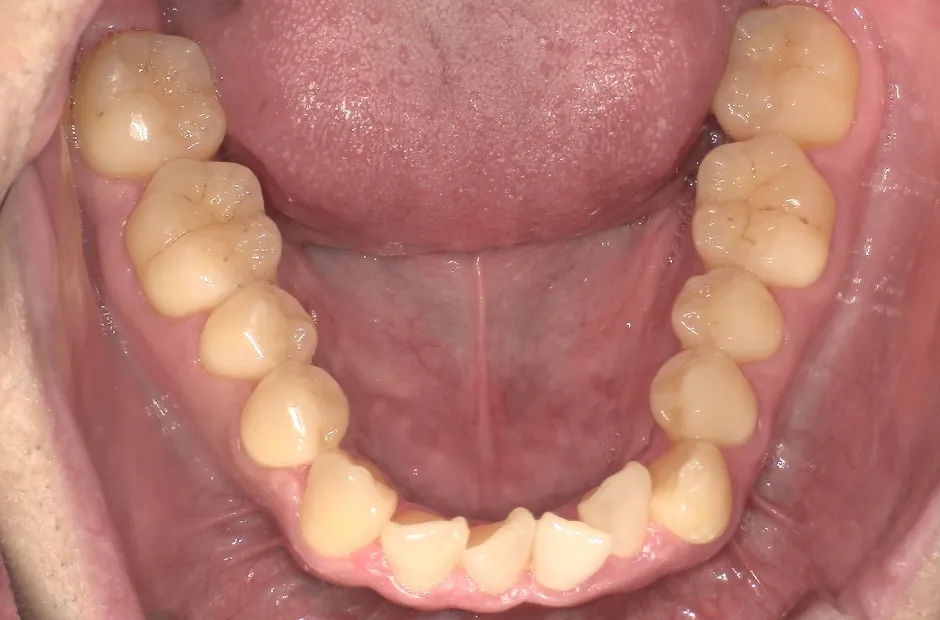

叢生

| 診断名・主訴 | 叢生 |

|---|---|

| 年齢・性別 | 43歳・女性 |

| 治療期間・回数 | 2年7か月 27回 |

| 治療に用いた主な装置 | 舌側矯正 |

| 抜歯部位 | 両顎4,4 |

| 治療費 | 100万円(税抜) |

| リスク・副作用 | 装置による違和感・疼痛・歯肉退縮・歯根吸収・虫歯のリスクなど |

治療前